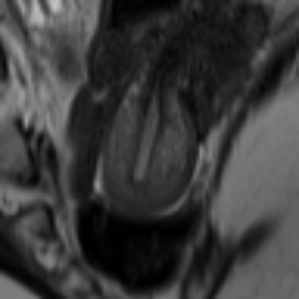

Image Reconstruction and Generation. Fig. 3 (left): Using LPIPS (AlexNet), the AE trained on FUNDUS achieved a score of on both full volumes and central slices (Z0), while the VAE reached . Applying ROI cropping to FUNDUS increased LPIPS to for the AE and for the VAE. All UMD inputs were evaluated without cropping to ROI. We evaluated 2D and 3D DDPMs using FID and LPIPS across uterine orientation classes and conditioning setups (Tab. 1): class only, class + ROI, class + text (C+T), and C+T + ROI. Example images for qualitative evaluation are shown in Fig. 2. All 2D models were trained on the central slices for evaluation, trained on all slices in the volume, FID and LPIPS increased by at minimum. Text-conditioned models without class-conditioning performed worse than class-only conditioned models in an extended ablation study. The 2D DDPM with C+T + ROI conditioning consistently achieved the best results. ROI cropping alone also improved performance, especially when combined with semantic input. In 3D, the best results came from class + ROI, though overall quality lagged behind 2D models. In Tab. 2, the ablation study shows that conditioning with class and text information combined with ROI preprocessing consistently improves image quality across DDPM and LDM models, with 2D LDMs achieving the best overall FID and LP scores.

Synthetic Datasets. The SynthUterus datasets include scans with synthetic images per class for each uterine position and are balanced to match the FUNDUS dataset distribution (Fig. 1). Two versions were generated using class and text conditioned DDPMs: full images referred to as SynthUterus and uterus-focused region of interest crops referred to as SynthUterus ROI, capturing semantic and spatial details to improve training. Ten real and ten synthetic healthy pelvic ROI MRI samples were classified by three groups: non-expert AI researchers, less experienced radiologists and experienced pelvic radiologists. Their accuracies were , and respectively, showing limited ability to distinguish real from generated images.